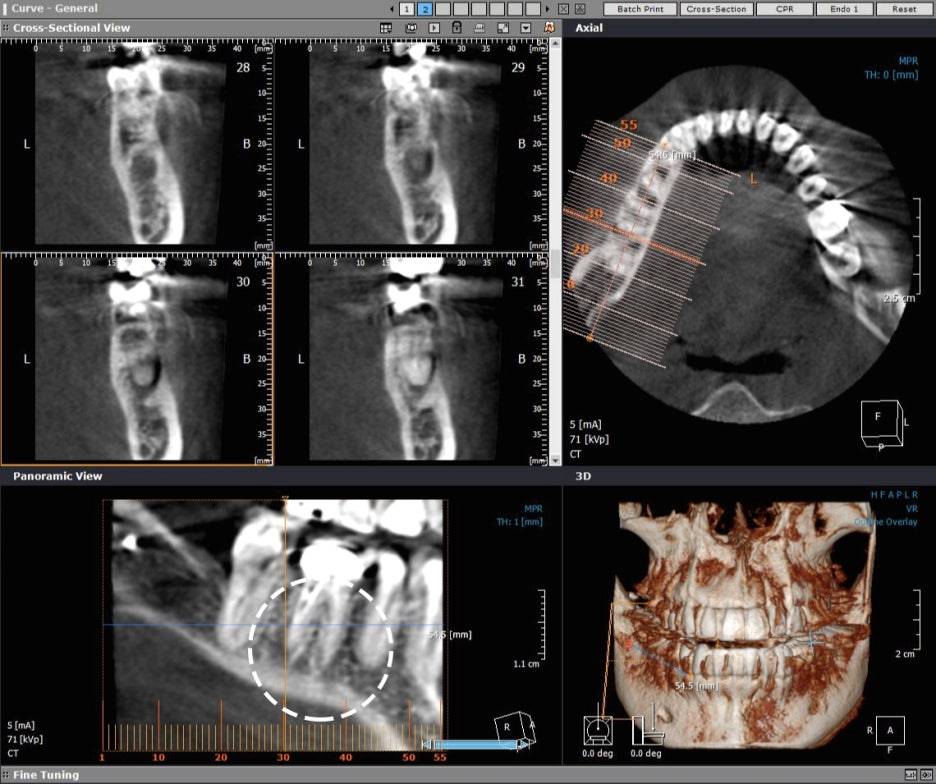

우선 잇몸 안쪽에 어떠한 문제가 생겼을 경우 외부의 색 변화나 통증이 느껴질 정도라면 이미 안쪽에서 염증이 많이 발생하였고 꼭 치료를 해야한다고 할 수 있겠어요. 보시는 것과 마찬가지로 잇몸에 염증으로 가득차서 튀어나와 있는 모습을 확인하실 수 있을텐데요. 이렇게 육안으로 보일 정도로 티가 나게 될때 까지 방치한 경우에는 한시라도 빨리 병원에 내원하시는 것이 좋습니다. 우선적으로 잇몸이 부었을 때에는 휴식을 취하거나 몸의 컨디션을 회복하면 금방 잇몸에고름이 가라앉기도 하였지만, 이런 상황이 반복되거나 쉽게 가라앉지 않고 고름이 커지거나 터지는 경우, 심지어 피가 나는 경우에는 그냥 내버려 두면 쉽게 가라앉지 않고 염증을 더 키워 나중에는 치료할 때에 더 애를 먹었었는데요. 그러다 보니 잇몸에 이러한 고름이 생기는 원인을 정확하게 파악해서 그에 맞는 치료를 제대로 받는 것이 재발을 방지하고 건강한 치아와 잇몸을 유지하는 데 도움이 되었었어요.

치주낭종이라 불린다는 잇몸고름주머니는 치아 신경조직이 세균에 감염되면서 치아 뿌리에 생긴 염증이 잇몸뼈를 뚫고 튀어나오는 현상이었는데요. 여기서 낭종이란 액체나 반고체의 물질이 들어 있는 주머니 모양의 혹으로 몸 어디든지 생길 수 있는 것인데 잇몸염증이 생겨 치아에 생겨난 낭종인 것이었지요. 주변의 조직보다 높은 삼투압에 의해 조직 사이의 액이 모이고 모여서 커지게 되는 것이었어요. 대부분 이 뿌리 끝 염증 속 고름은 빠져나오다 보니 생기더라도 통증이 없어 칫솔질을 하거나 혀로 잇몸을 건들 때 발견하곤 하였는데요. 이런 고름이 통로가 막혀 나오지 못하는 경우 통증이 생기고 내버려 두는 경우 냄새는 물론 이가 시리거나 악화하면 이가 흔들리고 음식을 씹을 때조차 통증으로 음식 섭취를 하는 그것조차 힘들게 되는 경우가 있었어요.

잇몸고름주머니가 생기는 원인은 충치인 경우가 일반적이었는데요. 충치가 심해지면 치수 조직까지 염증이 퍼지게 되고, 치수 조직이 괴사하고 치아 뿌리까지 염증이 생기게 되어 잇몸염증이 점점 커지면서 잇몸뼈를 뚫고 나오면서 생기는 것이었어요. 또 다른 원인은 충치 수복 물이 신경을 계속 자극하면서 치수 조직이 괴사하는 경우였는데요. 세균 감염이 일어나 치아 뿌리에 염증을 일으켜 치아낭종으로 이어지는 것이었어요. 그리고 치주질환이나 매복 사랑니에 의해서도 생길 수 있었는데요. 이때 주머니안의 고름을 없애주기만 해도 해결이 가능하기도 하였지만 매복 사랑니의 경우에는 통증이 발생하는 경우가 대부분이라 염증을 가라앉힌 후에 발치하여 윗몸고름주머니치료를 하기도 하였었어요. 또한 치과에서 흔히 치료를 하는 신경치료도 원인이 될 수 있었는데요. 신경치료가 제대로 진행되지 않아 치아의 신경 속에 세균이 침투하여 다시 감염이 일어나 치아 뿌리에 염증을 일으켜 잇몸에고름이 발생하는 것이었지요. 더불어 신경치료를 받았었는데 재발하거나, 신경이 죽어서 치아 뿌리쪽에 염증이 생겨 잇몸에 고름이 차오르는 경우도 있었어요.

과거에 씌운 치아 또는 신경 치료했던 치아 뿌리 끝쪽에서 발생한 염증은 신경관 내의 감염을 막기 위해 세균을 없애야 했는데요. 씌운 치아라면 이것을 제거하고 신경치료를 진행하거나 이미 신경치료를 받았던 치아라면 재신경치료를 할 수 있었는데요. 이런 경우 기존에 씌운 크라운을 제거한 후에 신경관에 채워져 있는 충전재를 제거하고 오염 부위를 치아 염증 조직을 깨끗하게 제거하고 소독과 세척을 진행한 후에 새로운 충전재로 빈틈없이 밀봉한 후 새로운 크라운으로 수복하여 치료하였었는데요. 신경치료를 다시 하는 것은 기존 신경치료보다 까다롭고 어렵다 보니 양질의 진료를 받을 수 있는 곳이 필요했었는데요. 최신 트랜드와 치료방법, 첨단장비 등은 물론 전문 의료진의 풍부하고 더 많은 시술 경험과 노련함이 적절한 치료를 받는 기준에서 무엇보다 가장 중요한 것이었었어요.